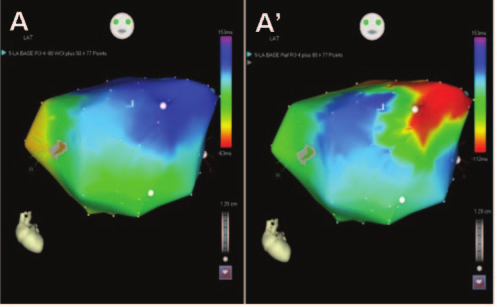

Voltage map

iwmi_isthmus.jpg

Voltage map in epicardium

lv_epi_lava.jpg